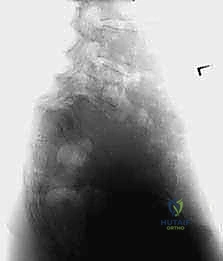

- الأشعة السينية الديناميكية (Dynamic X-rays): صور في وضعية الانحناء للأمام والخلف لتقييم مدى عدم استقرار الفقرات وحركتها غير الطبيعية.

يُعد الانزلاق الفقاري عالي الدرجة (High-Grade Spondylolisthesis) من أعقد الحالات الطبية وأكثرها تحدياً التي تواجه جراحي العمود الفقري على مستوى العالم. يتطلب هذا المرض فهماً تشريحياً دقيقاً، وتخطيطاً مسبقاً، وخبرة جراحية استثنائية لضمان استعادة المريض لحياته الطبيعية وتجنب المضاعفات العصبية الوخيمة التي قد تؤدي إلى الإعاقة الدائمة. تحدث هذه الحالة المتقدمة عندما تنزلق إحدى فقرات العمود الفقري إلى الأمام فوق الفقرة التي تليها بنسبة تتجاوز 50% من عرض الفقرة السفلية (الدرجة الثالثة والرابعة والخامسة).

في الانزلاق عالي الدرجة، يتجاوز هذا الانزلاق نصف مساحة سطح الفقرة. هذا التحرك الميكانيكي العنيف يؤدي إلى شد وتمزق الأربطة المحيطة، وتدمير القرص الغضروفي، والأخطر من ذلك؛ تضييق الخناق على الحبل الشوكي والأعصاب المتفرعة منه، مما يفسر تنوع وشدة الأعراض التي يعاني منها المريض.